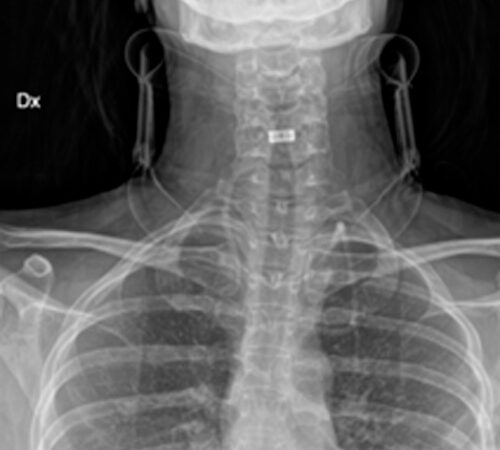

DIAGNOSI:

Ernia discale cervicale c5-c6

Risonanza magnetica cervicale pre-operatoria

Intervento chirurgico eseguito:

Microdiscectomia cervicale con approccio anteriore + introduzione di cage intersomatica cervicale

Radiografia cervicale post-operatoria